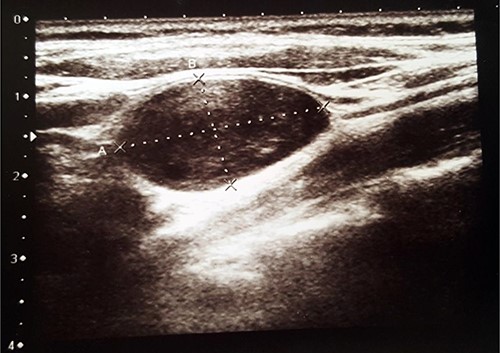

Histopathological examination revealed typical features of schwannoma (Figs 2 and 3). Tumour was well demarcated, encapsulated, composed of spindle cells, organized in a palisading fashion and had hypocellular myxoid component with large vessels. Tumour cells had an ill-defined cytoplasm and elongated nucleus. There was no mitotic activity.

Nuclear palisading around fibrillary process (Verocay bodies) is seen in cellular area; cells are narrow, elongated and wavy with tapered ends interspersed with collagen fibres.

Macroscopically schwannoma looks like yellowish-white, well-circumscribed mass [1, 6]. Microscopically, the baseline features of schwannoma are Antoni type A tissue and Antoni type B tissue [1, 4]. Necrosis, haemorrhage and cystic degeneration are other specific features [1, 4].